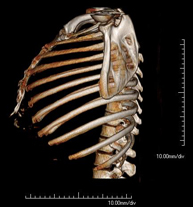

- TC Parrilla costal

Exploración radiológica que mediante un sistema de rayos X y detectores que giran alrededor del paciente, reconstruyendo las imágenes por ordenador, permite el estudio detallado de la parrilla costal.